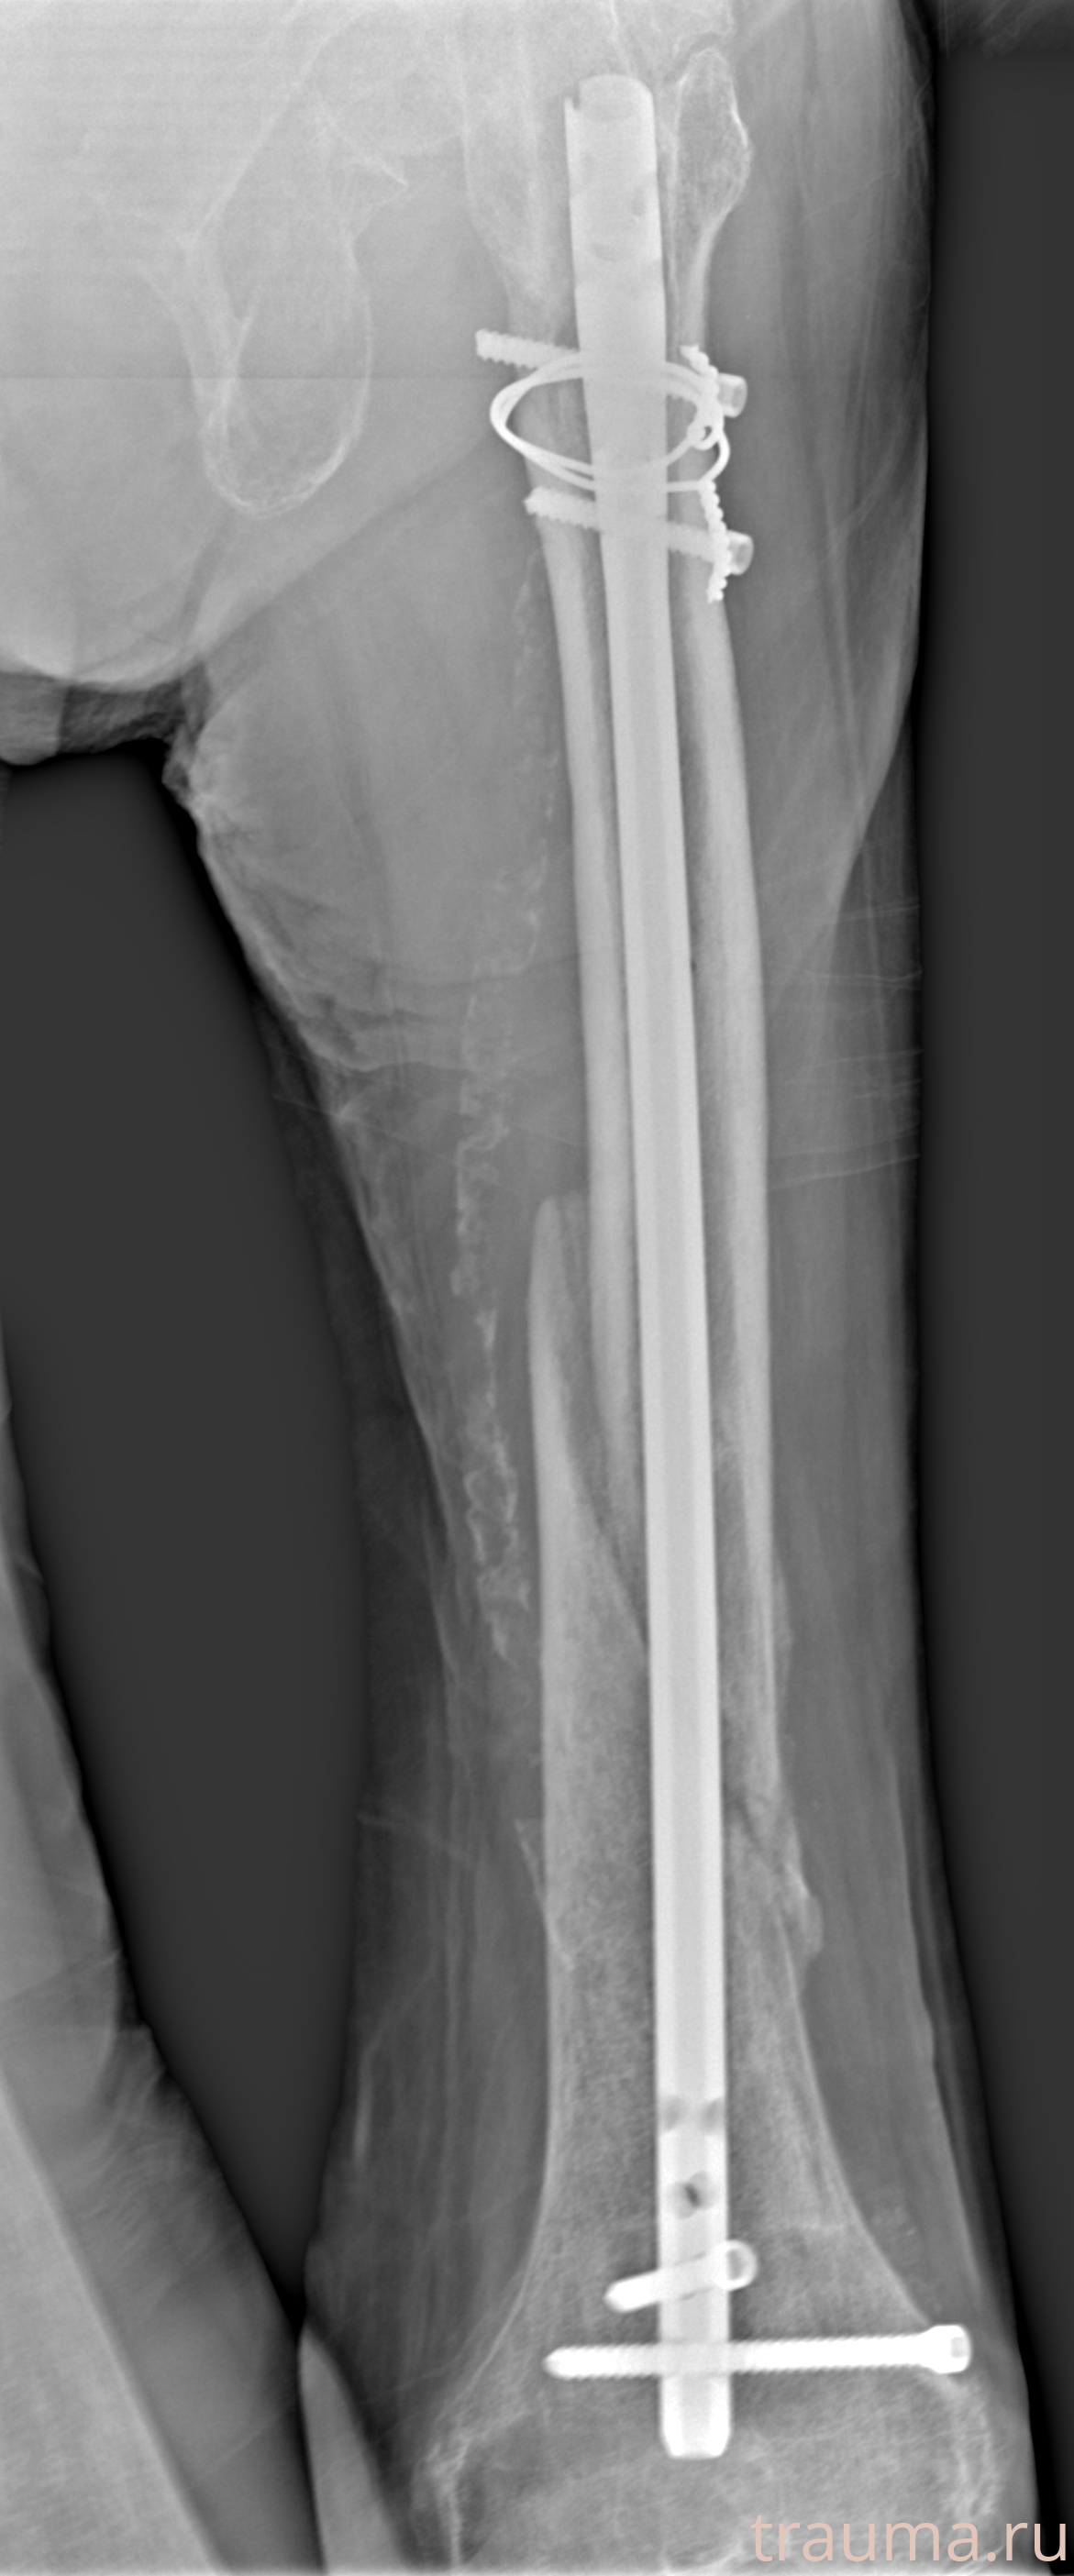

Рентгенограммы

Рентген на дому: по вашему адресу приезжает врач-рентгенолог, травматолог-ортопед с мобильным рентгеновским аппаратом, проводит диагностику травмы или заболевания, делает необходимые рентгенограммы, дает рекомендации по дальнейшему лечению. Получить качественные снимки в домашних условиях возможно благодаря уникальной методике, разработанной МосРентген Центром для института  Склифосовского